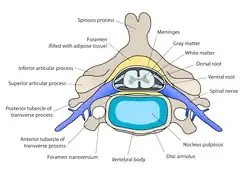

Les disques intervertébraux sont constitués d'un anneau fibreux externe, l'annulus fibrosus, qui entoure une substance gélatineuse interne, le nucleus pulposus[1].

- L'anneau de cartilage fibreux (en latin : annulus fibrosus) se compose de plusieurs couches (lames) de fibrocartilage constitué de collagène de type I et de type II. Le type I est concentré à l'extérieur de l'anneau conférant une grande solidité.

- Le noyau gélatineux ou noyau pulpeux (en latin : nucleus pulposus) permet lui de distribuer uniformément la pression sur tout le disque et empêche le développement de contraintes qui pourraient endommager les deux vertèbres sous et sus-jacente. Le nucleus pulposus contient des fibres en suspension dans un gel de mucoprotéine. Le noyau du disque agit donc comme l'absorbeur des chocs engendrés par l'activité physique de l'organisme et empêche les impacts entre les vertèbres.

- L'anneau fibreux a pour rôle de compartimenter le gel absorbeur de choc du noyau gélatineux. Il est solide et relativement rigide grâce à sa composition en collagène I et II.

- Le noyau pulpeux (ou gélatineux) se compose de grandes vacuoles de cellules d'origine notochordale, de petites chondrocytes, de fibre de collagène, et de protéoglycanes pouvant s'agréger en se liant à l'acide hyaluronique. Cette liaison forme des glycosaminoglycanes (GAG) pouvant être des sulfates de chondroïtine ou des sulfates de kératane[4]. Ces GAG dit "sulfatés" sont chargés négativement et ont la capacité de retenir l'eau dans les tissus. La quantité de glycosaminoglycanes (et donc d'eau indirectement) dans le noyau gélatineux diminue avec l'âge favorisant les phénomènes de dégénérescence[5].

La hernie discale se produit lorsque des pressions mécaniques déséquilibrées engendrent la déformation de l'annulus fibrosus, provocant un déplacement d'une partie du noyau gélatineux. Ces événements peuvent se produire à cause d'efforts physiques trop intenses causant une carence en vitamines C, de traumatismes ou à la suite d'une détérioration chronique (généralement caractérisée par une mauvaise posture et associée à des infections Propionbacterium d'acnes).[6] L'annulus fibrosus déformé et le gel du noyau gélatineux vont créer des contraintes latérales et/ou postérieures, gênant les fonctions musculaires proches et appliquant une pression sur les nerfs à proximité (symptômes typiques de racine nerveuse comprimées). Ces symptômes peuvent varier entre la paresthésie, des engourdissements, des douleurs aiguës et/ou chroniques (soit localement, soit au niveau du dermatome desservi par les nerfs piégés) et la perte de tonus musculaire. Le disque ne glisse pas physiquement; il possède seulement des renflements (généralement dans une seule direction). Le syndrome de la queue de cheval peut apparaître à la suite d'une hernie discale.